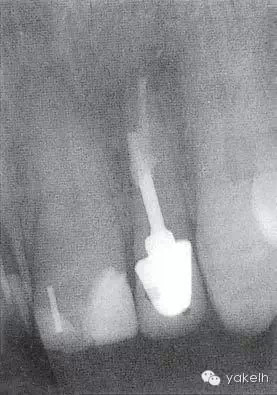

QQ圖片20150711144130.png

圖 5.4.1(b)22根尖X線片,顯示樁穿孔側(cè)方的根周透射影。